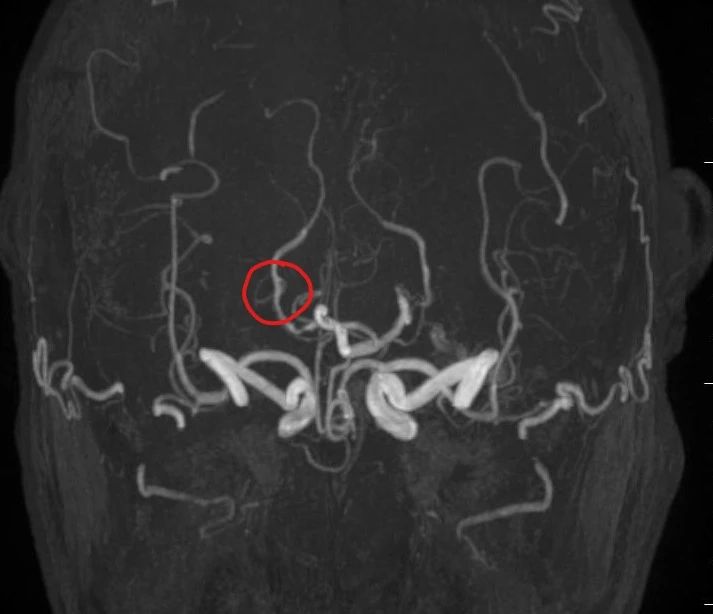

高场强设备(如3.0T MRI)提供更高分辨率的图像,能清晰显示血管狭窄、动脉瘤(≥3mm)、血管畸形等病变。研究显示,其对缺血性脑血管病的诊断灵敏度达95.2%,优于低剂量CTA。

一次检查可同时观察头颈部动脉主干及分支,结合平扫还能评估周围脑组织是否受损(如缺血灶),适合筛查脑卒中或复杂血管病变。